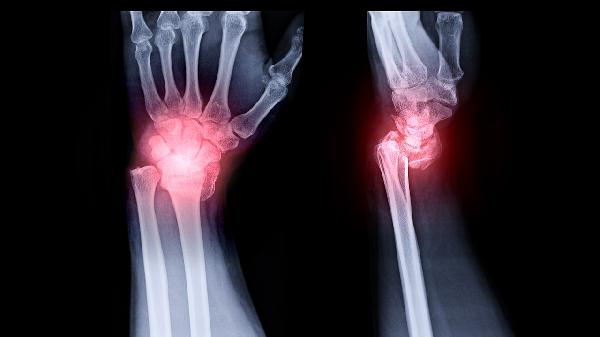

孤立性骨囊肿在超声图像上呈现为圆形或椭圆形的无回声区域,囊壁光滑且与周围骨组织分界清楚。由于囊内充满清亮液体,超声波穿透性良好,后方常出现回声增强效应。部分病例可见邻近骨皮质变薄甚至轻度膨胀,但无实质性肿块或血流信号,这一特点可与骨肿瘤区分。当囊肿合并出血或感染时,内部可能出现细密点状回声。

少数情况下超声可能显示囊内存在分隔或少量沉积物回声,此时需警惕病理性骨折风险。若发现骨皮质不连续或周围软组织水肿,提示可能存在并发症。对于位置表浅的骨囊肿,高频超声能清晰显示骨膜反应和微小骨折线,而深部病灶可能需要结合X线或CT进一步评估。